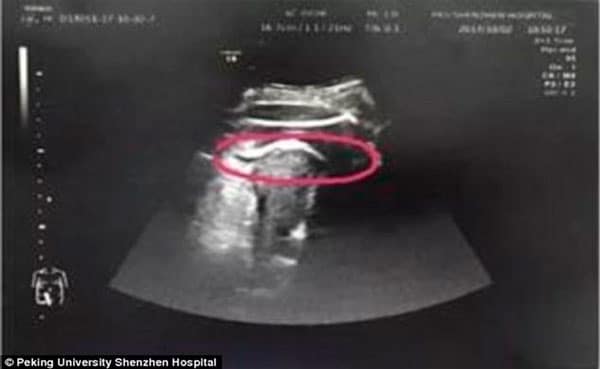

Ela, que estava na 35ª semana de gestação, passou mais de 5 horas com dores abdominais muito fortes e resolveu procurar ajuda médica, no dia 2 de outubro. Para sua surpresa e da equipe que a atendeu, o exame de ultrassonografia constatou que seu bebê acabou perfurando seu útero com a perninha!

O caso foi relatado pelo Hospital Universitário de Pequim essa semana, que afirmou que tanto a mãe quanto o bebê passam bem após uma cesárea de emergência, pois o líquido aminótico vazou pela cavidade abdominal da gestante. Aparentemente, há uma explicação racional para o caso: no ano passado, Zhang teve um fibroma, espécie de tumor benigno, em seu útero e após seis meses ela descobriu que estava grávida, logo, os médicos acreditam que quando a criança chutou a mãe, ela acabou acertando o local desse fibroma e rompido o útero por consequência.

Foto: Reprodução/ Internet/ Peking University Shenzhen Hospital